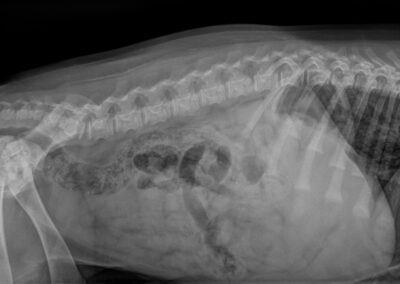

HD:

ED:

rug: 100%

Spondylose: vrij